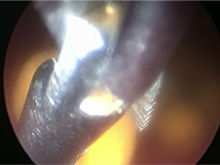

尿道内の石を確認しカテーテルで膀胱内に押し戻した様子